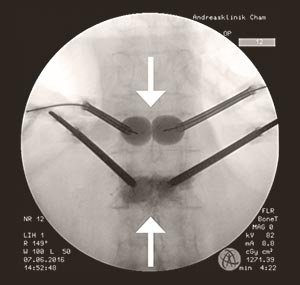

Intraoperative Aufnahme der Wirbelsäule von hinten. Im oberen Wirbel die gefüllten Ballone, unten die Zementplombe.

In dieser Situation wurde Esther Kaltbach die operative Behandlung der gebrochenen Wirbelkörper empfohlen. Mit einer sogenannten Kyphoplastie, einem minimalinvasiven Eingriff, kann die Schmerzursache rasch und effektiv behoben werden. Dabei wird je eine Nadel rechts und links in den betroffenen Wirbelkörper eingestochen und mit einem Ballon aufgerichtet. Der so entstandene Zwischenraum wird mit Knochenzement und -kalk aufgefüllt. Der Eingriff dauert rund 30 Minuten und wird in der Regel in Narkose durchgeführt. Der Knochenzement härtet nach 20 Minuten aus, so dass die Patienten rasch aufstehen können. Eine Spitalentlassung erfolgt am Folge- oder am übernächsten Tag.